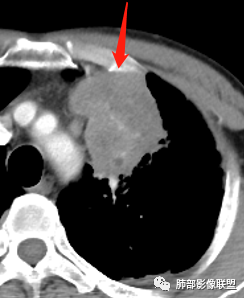

中年男性,咳嗽咳痰一月。左肺上叶团块状软组织密度影,边缘部分清晰周围见磨玻璃影,增强后其内密度不均可见散在斑片状低密度区,血管造影征完整,团块邻近胸膜可见多发圆形低密度透光灶。左肺门处上叶血管似被包绕。左侧胸膜粘连肥厚。考虑1.左肺占位,淋巴瘤?鳞癌?2.因病灶内散在低密度待除外感染性病变可能

患者中年男性,咳嗽、咳痰1月余入院。胸部CT:左肺上叶尖段近胸膜下肿块占位灶,边缘光滑,边界清楚,周围可见片状磨玻璃影,可见平直、毛刺、分叶征象,增强轻度强化,内可见点片多发低密度区及部分血管影,与支气管关系欠清,左肺上叶背侧胸膜增厚、胸膜下结节,右肺似见多发小结节灶,淋巴结不大。综合考虑良性病变,结核可能性大,鉴别腺癌并肺内、胸膜转移及淋巴瘤等。

男,47岁,咳嗽咳痰一月。病灶位于左内乳动脉内缘,定位肺内,呈团片状异常密度影,整体沿支气管气管束走形分布,由肺门达胸膜下,于近肺门侧病灶形态相对较小,病灶远端相对较大,病灶整体密度偏均匀,强化偏明显,病灶内见多发支气管扩张并粘液栓形成,且扩张支气管粗细不均,直达病灶以远,病灶内血管走形正常、粗细均匀,病灶周围见边缘模糊磨玻璃及少许腺泡结节。左肺门及纵隔略大淋巴结,左侧胸膜局限性增厚。诊断:左肺上叶前段异常密度影,炎性肉芽肿性病变可能,结核不能除外,建议穿刺活检除外恶性肿瘤。

4.病灶整体轻中度强化,强化较均匀,局部见多个管状低密度影,边界清,考虑支气管粘液栓;病灶局部可小灶样的低密度区,未见强化,考虑坏死灶,坏死灶周围见明显强化的壁,壁清楚、光整,未见中断,倾向炎性肉芽肿的坏死;

6.病灶与纵隔胸膜呈“糊墙”样改变,倾向炎性病灶;